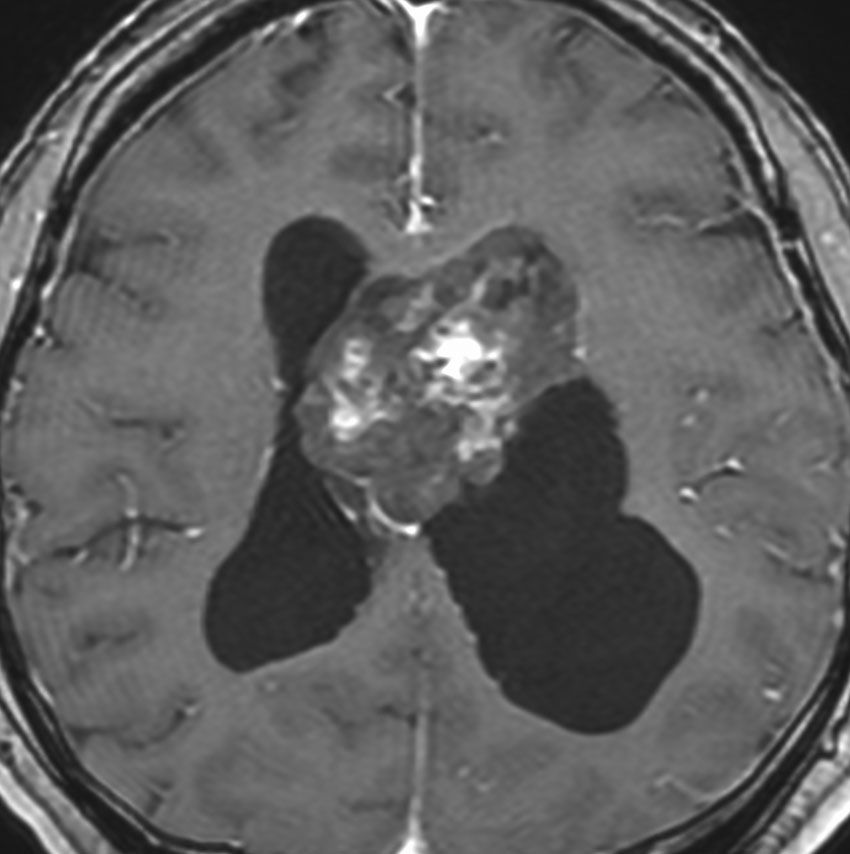

巨大な上衣下腫,でも良性のもの

52歳の男性で,2008年に脳ドックで見つかって無症状でした。中枢性神経細胞種 central neurocytomaを疑いましたが,上衣下腫 subependymomaはまったく考慮に入れませんでした。壮年男性でしたから経過観察しました。右側は2019年,11年後のものです。徐々に増大して水頭症になり歩行障害がでてきました。

手術前の画像です。血管が豊富で大きな導出静脈がみられ,腫瘍内出血もあります。ガドリニウムでは部分的に増強されます。CISS/FIESTAの画像では,透明中核から発生したようにみえて,脳浸潤は全くありません。脳弓は腫瘍の底面にありますが,もちろん境界はっきりしません。これらもcentral neurocytomaの画像所見として捉えられるものです。

transcallosal approach 経脳梁法で亜然摘出しました。底面には脳弓があって剥離できないから全摘出はできません。病理所見は,のう胞形成を伴う線維性基質の中に楕円形の細胞が索状または小巣状に増生するものでsubependymomaと診断されました。異型は軽度で,核分裂像はなく,MIB-1染色率は1%以下のWHO grade Iの所見。EMAは細胞質にdot likeに陽性でしたがわずかであり,ependymomaとの合併腫瘍の診断には至りませんでした。

術後1年の画像です。無症状で復職できています。